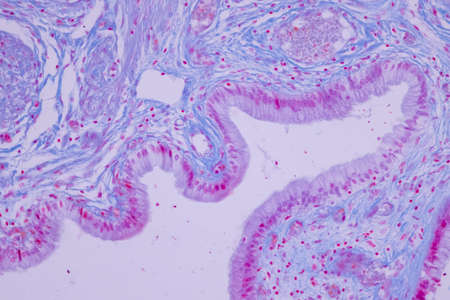

Histopathology of prostate gland hyperplasia, light micrograph, photo under microscope

High magnification of a human prostatic gland. A simple columnar epithelium surrounds a very irregular lumen. Hematoxylin & eosin stain.

Photomicrograph showing histological features of benign prostatic hyperplasia. Enlarged prostate gland with nodular proliferation of glandular and stromal components.

Photomicrograph showing histological features of benign prostatic hyperplasia. Enlarged prostate gland with nodular proliferation of glandular and stromal components.

Low magnification of a human prostate gland in a 70-year-old man. The prostate gland appears with dilated alveoli, which contains many corpora amylacea (prostatic concretions) in their lumen. Light microscope micrograph. Hematoxylin & eosin stain.

Human seminal vesicle. The surface of the mucosa is very folded. The spaces that look like glands are really infoldings of the mucosa that communicate with the lumen. The epithelium is pseudostratified columnar with basal cells.